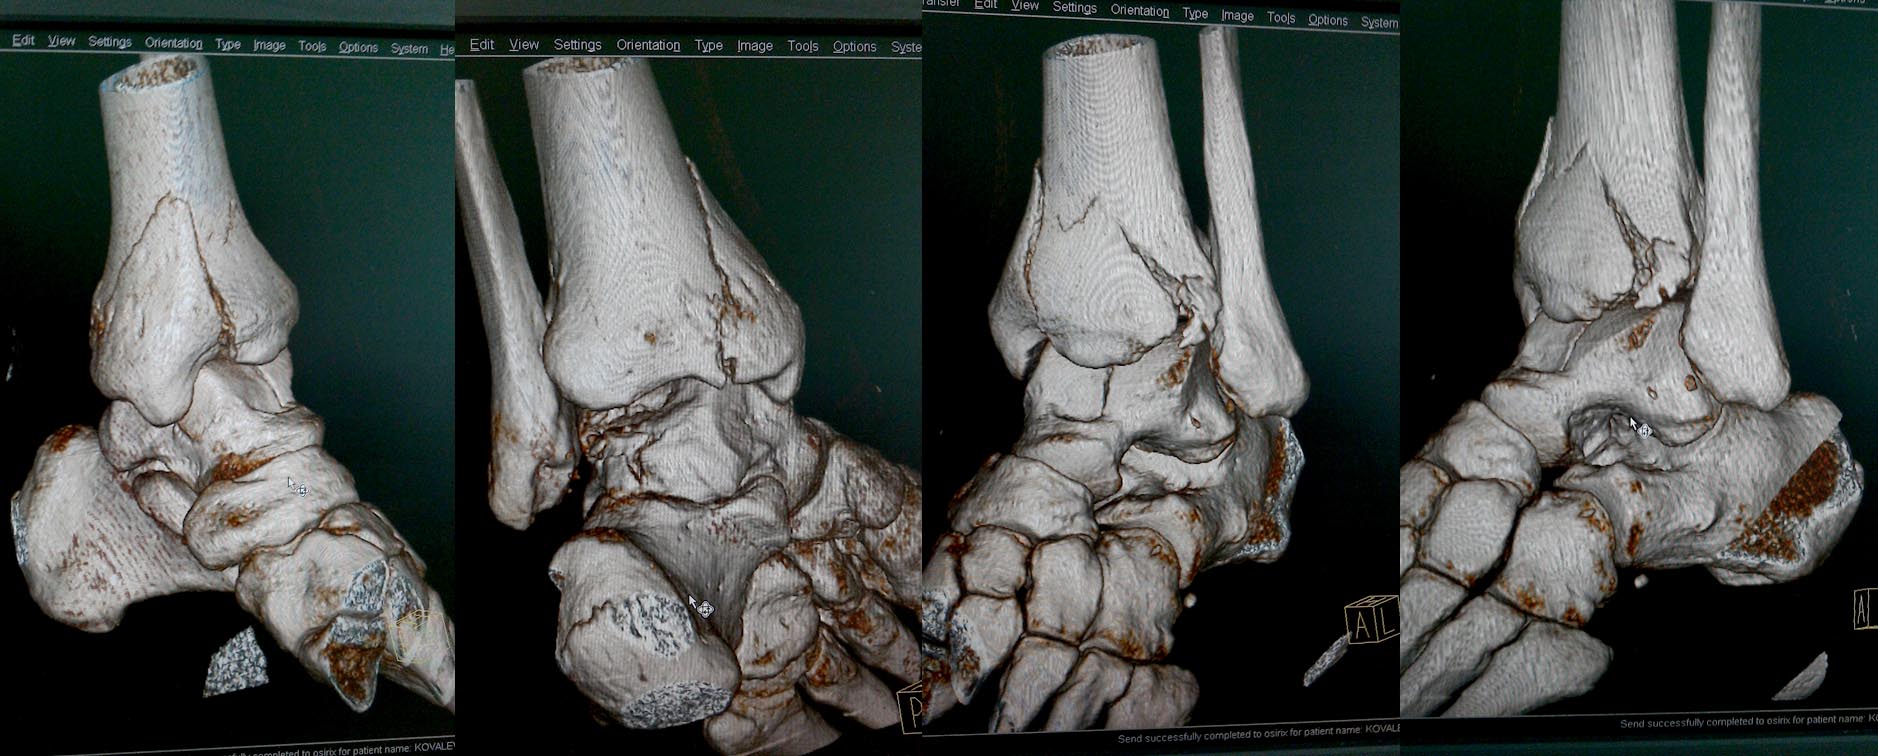

Re: перелом таранной кости и пилона

Кирилл, проблема ведь не только в таране, пилон тоже пострадал, ведь так? Дайте дистракцию на аппарате, может за счёт лигаментотаксиса что то встанет. А там подумать. Но напрашивается фиксировать передник край б/б кости, и затем добраться к тарану, доступ по данным срезам продумать сложно, может потребуется остеотомия наружной лодыжки, отломки тонким долотцом поднять, костная пластика дефекта, винты, в послеоперационном периоде опять аппарат. Уж больно куском много. Артродез то же не исключаю.

С пилоном тактика ясна, аппарат сразу не накладывал из-за приличного состояния мягких тканей и умеренного отёка, доступ к таранной кости возможно удастся через зону перелома пилона. А вот как зафиксировать фрагменты суставной поверхности тарана после репозиции?

Очень сложный перелом. И срезов маловато. Наверное нужно подумать над доступом, который позволит использовать имеющуюся линию перелома для подхода к суставной поверхности таранной кости. Через это доступ "поднять" вдавленные фрагменты с последующей костной пластикой образовавшихся пустот. Выполнить остеосинтез таранной кости винтами. И закончить остеосинтезом большеберцовой кости.

3D

поверьте, среди нас мало экспертов переломов таранной кости, ещё меньше - экспертов именно ТАКИХ переломов, а вот сочетание именно такого перелома с переломом пилона типа В - уж совсем редкость.